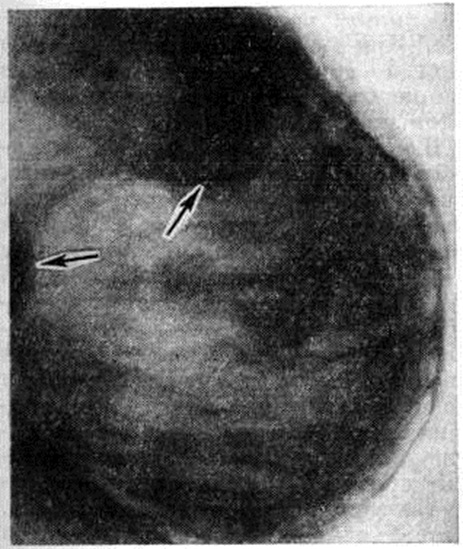

( A ) Синдром Поланда с полным отсутствием грудной мышцы и ткани молочной железы.Обратите внимание на расположенный сверху и гипоплазированный сосок и ареолу (перепечатано с разрешения Caouette-Laberge L, Bortoluzzi P. Коррекция асимметрии груди у подростков. В: Hall Findley E, Evans GRD, eds. Эстетическая и реконструктивная хирургия груди. Филадельфия, Пенсильвания. : Saunders Elsevier; 2010: 601–629). ( B ) Синдром Поланда с подмышечной перемычкой, отсутствием грудино-реберной грудной мышцы и гипоплазией молочной железы. (Перепечатано с разрешения Caouette-Laberge L, Bortoluzzi P. Коррекция асимметрии груди у подростков.В: Холл Финдли Э., Эванс GRD, ред. Эстетическая и реконструктивная хирургия груди. Филадельфия, Пенсильвания: Saunders Elsevier; 2010: 601-629.)

(Перепечатано с разрешения Caouette-Laberge L, Bortoluzzi P. Коррекция асимметрии груди у подростков.В: Холл Финдли Э., Эванс GRD, ред. Эстетическая и реконструктивная хирургия груди. Филадельфия, Пенсильвания: Saunders Elsevier; 2010: 601-629.)